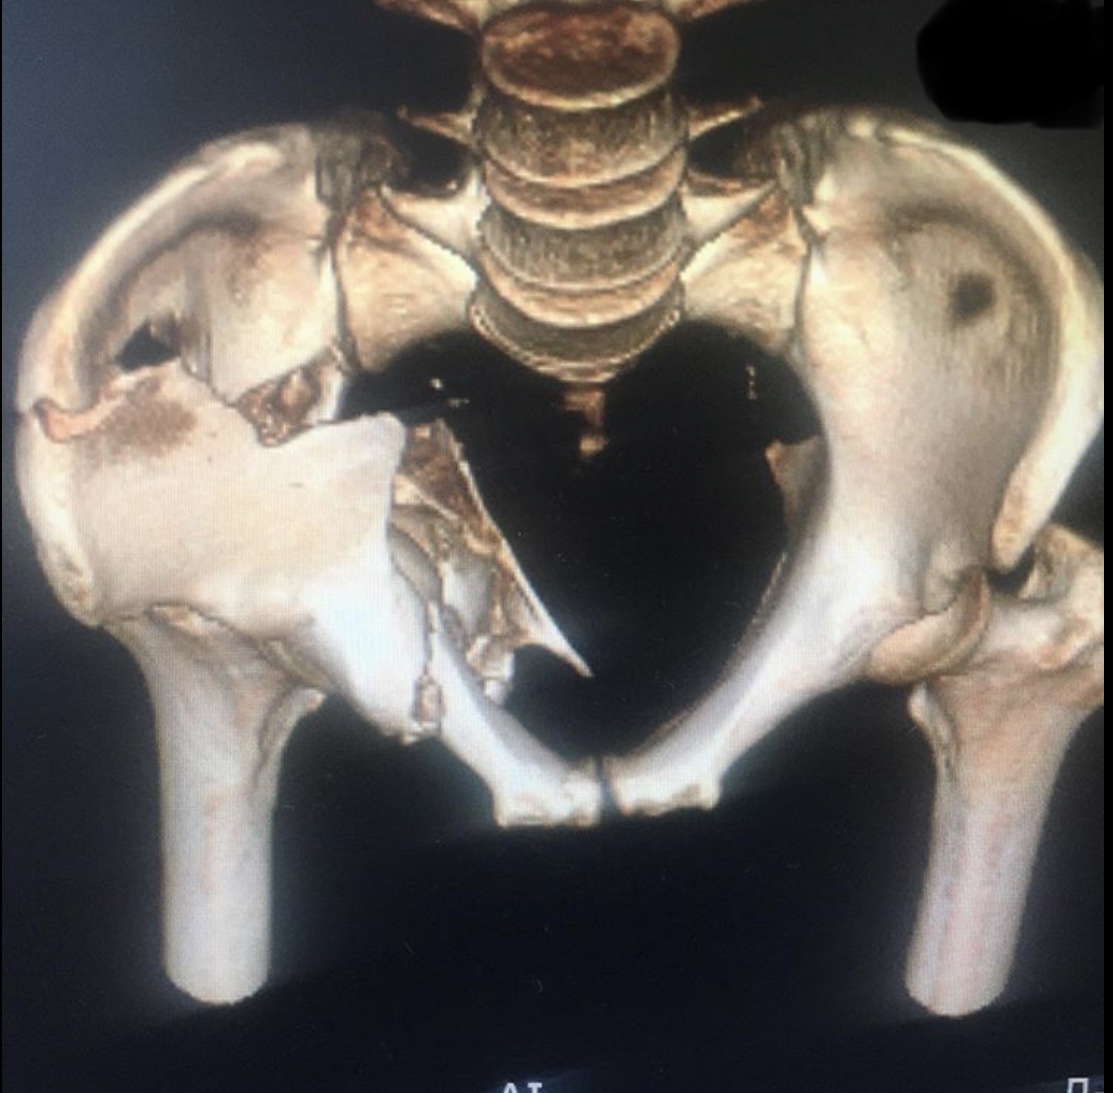

Ещё один случай тяжелой травмы вертлужной впадины с разнонаправленным смещением отломков.

Перелом вертлужной впадины со смещением – сложный перелом в области ямки тазобедренного сустава. Обычно возникает в результате воздействия сильной кинетической энергии, удара или падения, в группу риска входят спортсмены, частая травма при автомобильных авариях.

Сложность данного травматизма в длительном восстановительном периоде, высокой вероятности возникновения посттравматического коксартроза, который приводит к инвалидности пациента. Лечение перелома со смещением хирургическое в случае наличия вывиха сустава, крупных отломков костей, существует риск неполного восстановления двигательной функции.